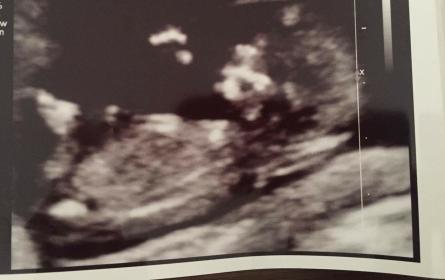

These pics are from 12 weeks 2 days . Im thinking girl but im not an expert. Would live some guesses please x Attachment 35635

Leaning boy from first pic - looks slightly angled to me

I think Boy too

Slight boy guess from me

Boy lean

Boy x

I'm leaning boy. :)

Update!! Baby is a girl!